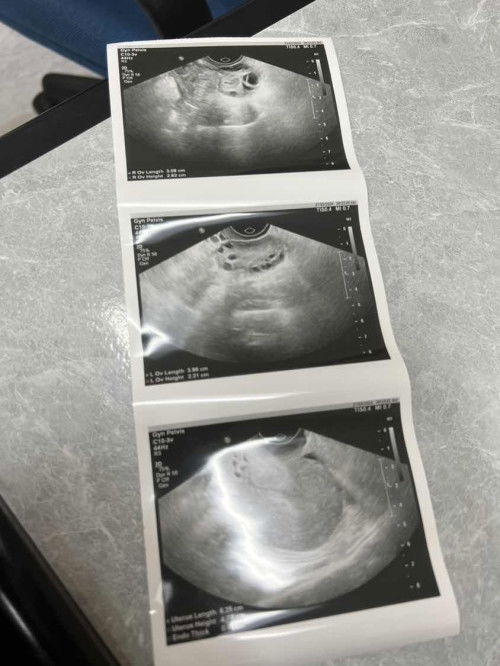

Saya nak tanya Gambar first :- telur kanan Gambar sec :- telur kiri 6tahun saya ttc, rabu last week saya jumpa pakar & scan Sebelum ni saya takpernah nampak telur yg normal sebab saya both side pcos! And last week telur kanan saya size normal 🥹 tapi tiub kanan saya block, tiub kiri ok.. adakah saya berpeluang tu mengandung secara normal? Next appointment saya kena buat iui 🥺 #ingintahu #SeriusTanya #bantusharing